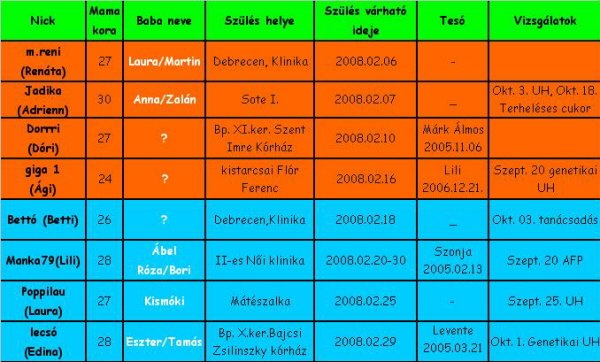

Lili!